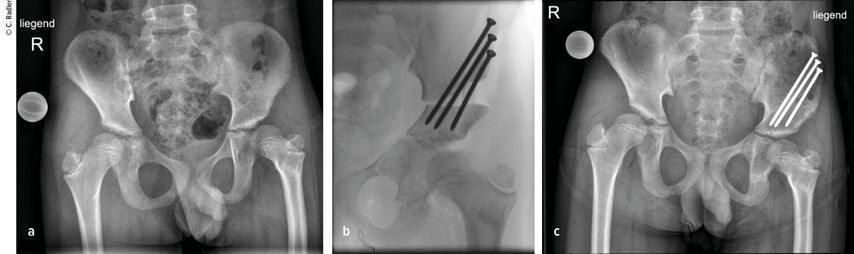

Milde Formen – Typ 1A – zeigen oft nur einen leichten Schenkelhalsvarus und eine verminderte femorale Antetorsion beziehungsweise Retroversion zusätzlich zur Verkürzung. Oft zeigt sich bei diesem Typ auch eine milde subtrochantäre Varusstellung und Sklerose. Mit zunehmendem Schweregrad addiert sich eine azetabuläre Dysplasie, wobei besonders die obere und hintere Überdachung der Hüfte vermindert ist. Beim Typ 1A ist in seltenen Fällen keine vorbereitende Operation erforderlich, insbesondere wenn die Überdachung der Hüfte sehr gut ist und ein CE-Winkel von über 20 Grad vorliegt. Es kann dann direkt mit einer Verlängerung des Femurs begonnen werden. Je nach verwendeter OP-Technik können eine eventuell vorhandene Retroversion und Varusstellung im Rahmen der Verlängerungsoperation akut über eine zusätzliche proximale Osteotomie und Montage an den oberen Teil des Fixateurs adressiert werden. (Abb.1).

Abb. 1: Operative Versorgung eines CFD rechts mit Varusstellung an der Hüfte und subtrochantärer Sklerosierung